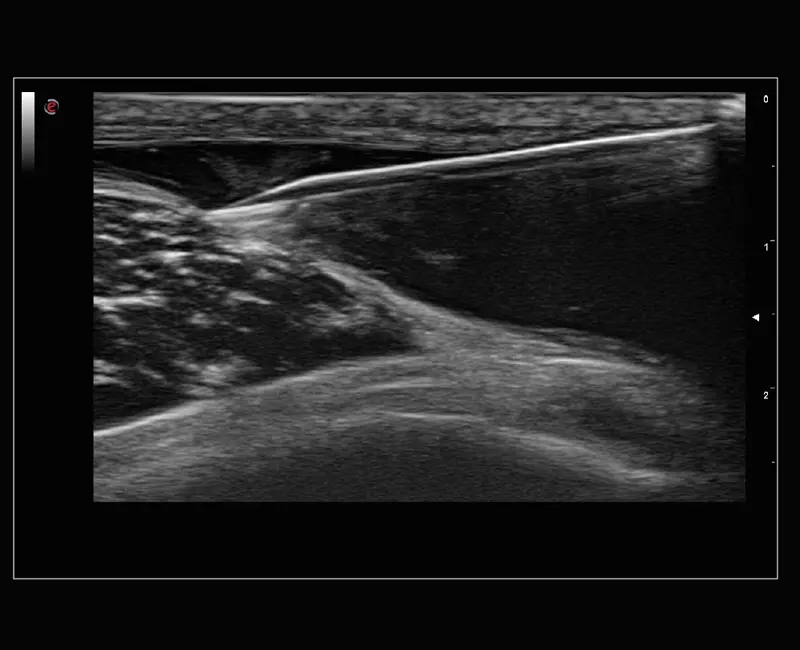

MyLab™Sigma Elite - Needle Enhancement for precise interventional procedures

MyLab™Sigma Elite - Needle Enhancement for precise interventional procedures